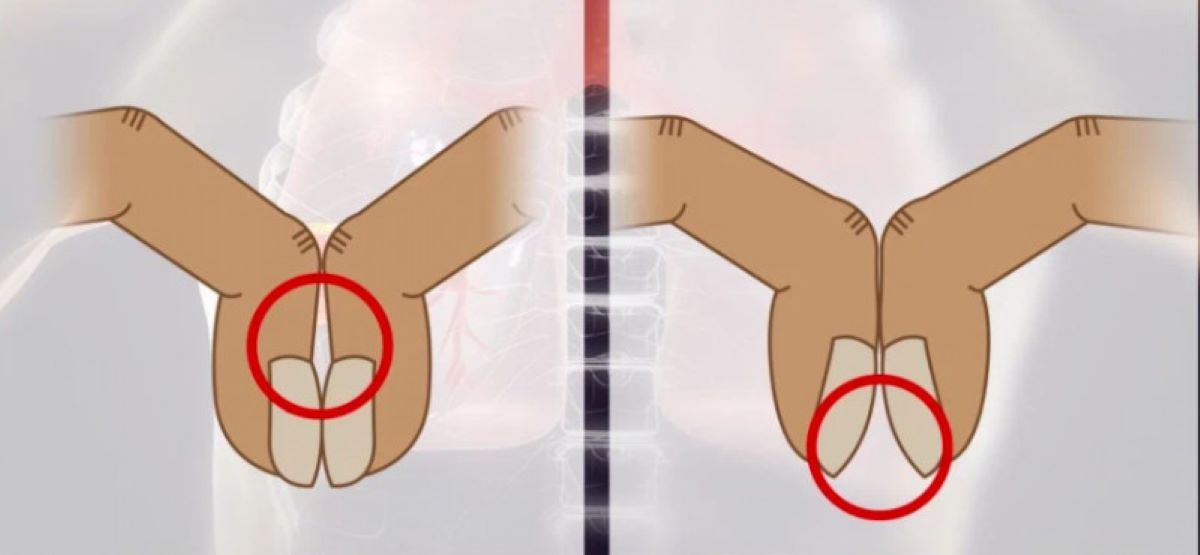

Testul implică alăturarea unghiilor de la degetul arătător pentru a verifica dacă între cuticule există un spațiu, care are cel mai des forma unui diamant, în cazul unei persoane care nu suferă de cancer la plămâni, potrivit Huffington Post.

Dacă nu există niciun spațiu între cuticule, acesta este un semn foarte comun al cancerului la plămâni. Astfel că dacă o persoană descoperă că nu are acest spațiu, ar trebuie să facă o vizită la medic pentru verifica sănătatea plămânilor. Acesta poate fi un simptom timpuriu al unei afecțiuni care deseori este fatală: cancerul la plămâni.